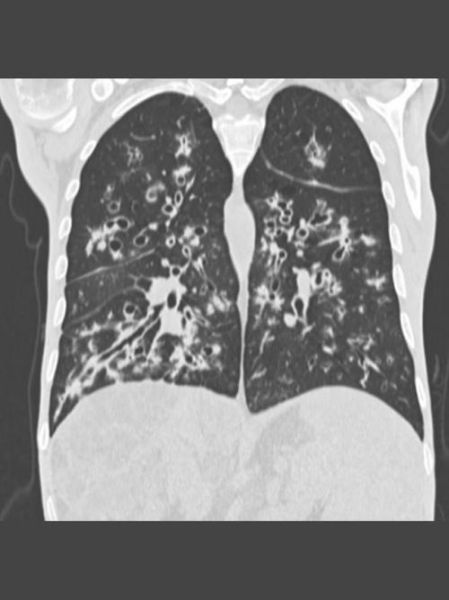

铜绿假单胞菌是CF患者肺衰竭主因。传统做法是长期吸入妥布霉素,但耐药率逐年攀升。

• 吸入型噬菌体:英国Great Ormond Street医院2022年报告,12例耐药菌患者接受个体化噬菌体后,痰菌载量下降2–3 log10

• 铁载体-抗生素偶联物(如Cefiderocol):利用细菌摄铁系统“特洛伊木马”式渗透,体外MIC值降低8倍

85% CF患者合并胰腺功能不全,脂溶性维生素缺乏导致骨质疏松、夜盲。